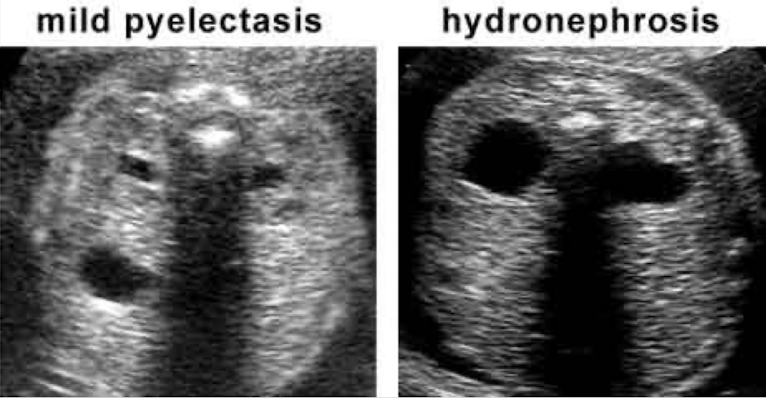

mild pyelectasis (dilation) vs. hydronephrosis in utero

before 27w = >4mm is abnormal

after 27w = >7mm is abnormal